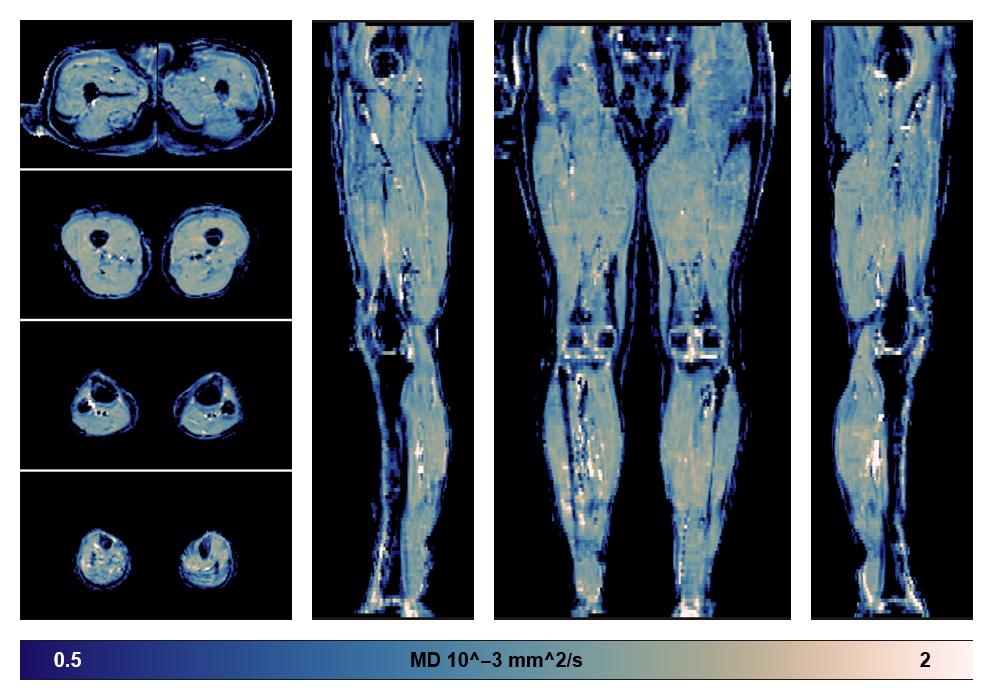

• Mean diffusivity

IVIM corrected whole leg muscle mean diffusivity obtained from diffusion tensor imaging.

• Fractional anisotropy

IVIM corrected whole leg muscle fractional anisotropy obtained from diffusion tensor imaging.